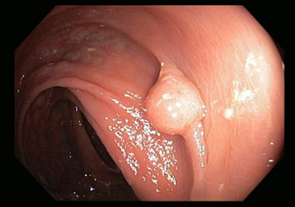

Premalignant lesions are described in terms of number, shape, size, location, histological type, and degree of malignancy. In terms of shape, the polyps were sessile, semipediculated or pedicled, round-oval, or polylobate (Figure 4).

B | |

C | D |

Fig. 4 Endoscopic appearance of polypsA – sessile polyp; B – semipediculated polyp; C – pedunculated polyp; D – voluminous villous polyp | |